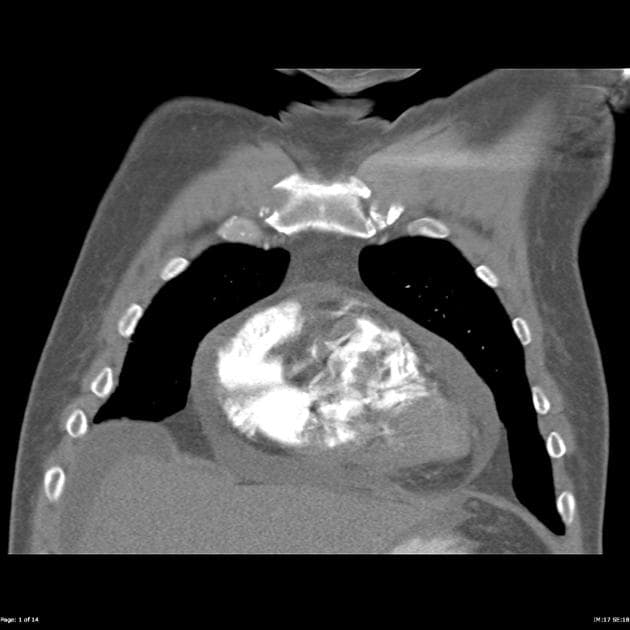

- Thấy khối hình polyp kích thước 38 mm ở đáy bàng quang, có ngấm thuốc, không lan ra ngoài bàng quang hoặc bệnh lý hạch vùng.

Khối bàng quang; được xác nhận bằng giải phẫu bệnh là ung thư tế bào chuyển tiếp (transitional cell carcinoma – TCC). Ung thư tế bào chuyển tiếp (TCC) là ung thư nguyên phát phổ biến nhất của đường tiết niệu và có thể xuất hiện dọc theo toàn bộ chiều dài của hệ thống này, từ bể thận đến bàng quang (bể thận: hiếm gặp, khoảng 2–3%; niệu quản: ít gặp nhất, khoảng 1%; bàng quang: phổ biến nhất, chiếm khoảng 97%).

- "Các đặc điểm hình ảnh của TCC bao gồm các khối hình polyp hoặc phẳng tăng ngấm thuốc trong lòng bàng quang, thường ở đáy hoặc tam giác bàng quang."